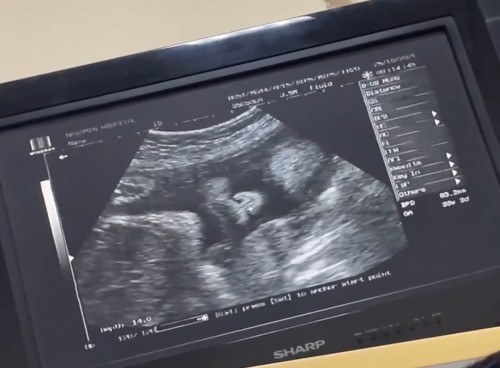

แม่บ้านไหนทีม ธันวา 64 บ้างค่ะ🥰. 😍😍😍😍😍 มาแบ่งปันรูปน่ารักของต้าวน้อยกันค่า😘😍😍😍😍 บ้านนี้ท้อง2 🤰🏼 ปู้ชาย แก่มป่องค่ะ 🥰😍😍😍😍😍 32w 🤰🏼🤰🏼🤰🏼😍😍😍😍😍😍